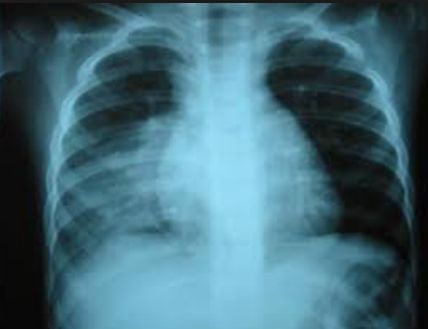

La neumonía alveolar (también denominada lobar, lobular o neumonía segmentaria) es en general causada por patógenos bacterianos, y Streptococcus pneumoniae en particular, sobre todo cuando se acompaña de recuento elevado de leucocitos periféricos, las concentraciones de proteína C reactiva (PCR) y fiebre alta, lo que justifica el tratamiento con antibióticos.

Según comentan los autores, Greenberg y col. 2013,  ningún estudio hasta la fecha ha utilizado una combinación de signos clínicos, hallazgos de laboratorio y la definición de la radiografía de tórax, para comparar la duración del tratamiento ambulatorio oral en la NAC  alveolar, en la infancia.

Para aumentar la probabilidad diagnostica de neumonía bacteriana, y minimizar la variabilidad entre los pacientes, se utilizaron criterios de selección predefinidos, que incluían radiografía de tórax, la temperatura corporal y hallazgos de laboratorio.